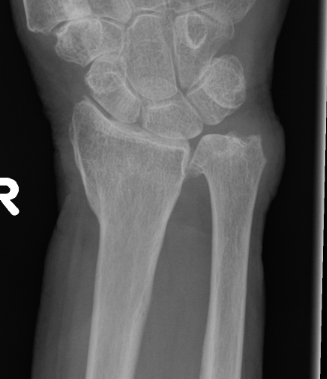

Xray

Bilateral xrays

PA film in neutral

- wrist neutral

- elbow & shoulder at 90°

Malunion

| Radial shortening | Radial inclination | Positive ulna variance |

| Dorsal tilt > 15 degrees | Volar tilt > 10 degrees | Articular step > 3 mm |

Pathology

Radial shortening

- affects normal kinematics of the DRUJ

- ulnocarpal abutment

Dorsal tilt

- loss of flexion

- +/- midcarpal instability - DISI / CIND without interosseous ligament disruption